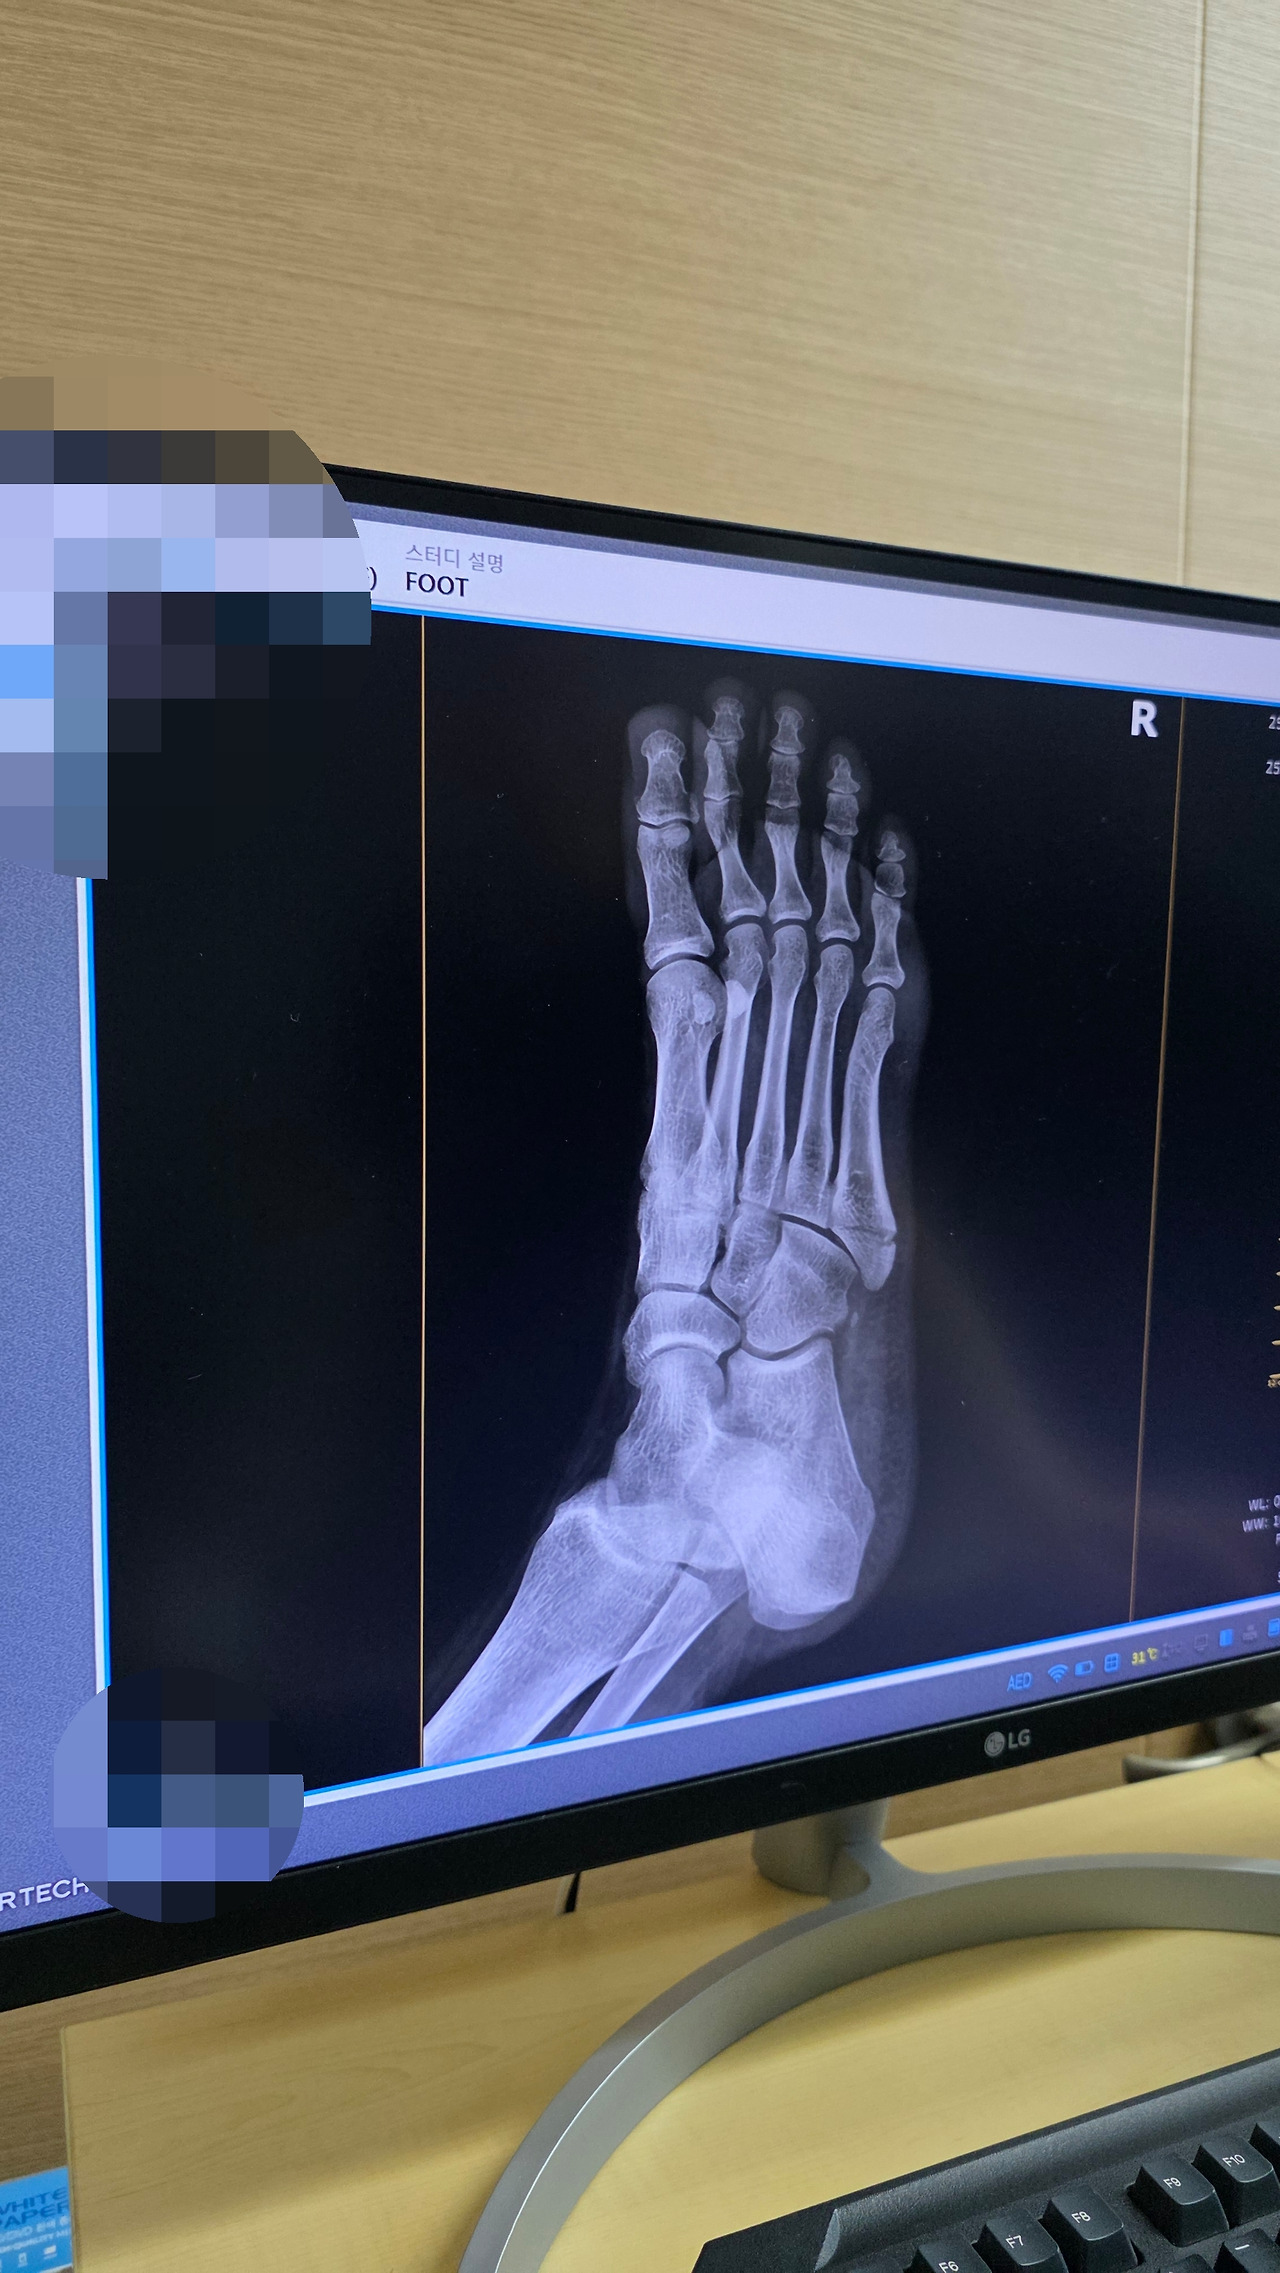

특히 제5중족골은

“Pseudo-Jones vs. Jones” 이렇게 나뉘는데

둘 다 발등 바깥쪽, 새끼발가락 근처 뼈가 부러지는 거지만

부러진 위치랑 각도, 치료법이 다르다고 한다.

(※정확한 진단은 엑스레이 + 의사 선생님 판단이 중요함)